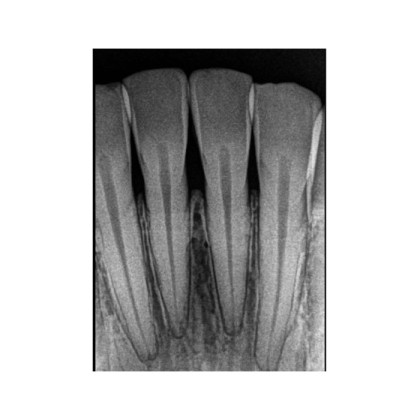

Реальное разрешение 16 пар линий/мм позволяет получать снимки с исключительной детализацией, что особенно важно для выявления кариеса, трещин и аномалий корневых каналов.

- Диагностика кариеса и его осложнений – выявление патологий на ранних стадиях.

⚙️ Передовые инструменты обработки изображений – улучшенная контрастность, фильтрация шумов, регулировка резкости для повышения качества диагностики.

| Разрешение пар линий | 16 |